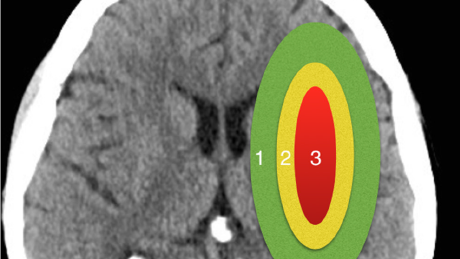

Перевод статьи Imaging assessment of acute ischaemic stroke: a review of radiological methods Aubrey George Smith, BSc, MBBS, MRCS, FRCR, Chris Rowland Hill, BA, MBBS, MRCP, FRCR British Journal of Radiology, Volume 91, Issue 1083, 1 March 2018, 20170573, https://doi.org/10.1259/bjr.20170573 Острый ишемический инсульт является второй по величине причиной смерти во всем мире и причиной серьезной физической и психологической заболеваемости. Современное лечение, основанное на доказательствах, включает...